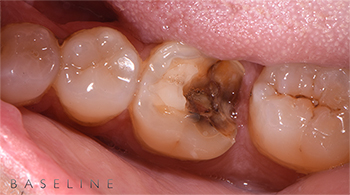

Il paziente, un uomo di 62 anni, si presentava alla nostra attenzione lamentando la frattura di un vecchio restauro in corrispondenza dell’elemento 4.6.

Tale valutazione delineava una frattura parziale della porzione occluso-distale dell’elemento 4.6 sottoposto anni prima ad un trattamento endodontico.

L’esecuzione di una radiografia endorale periapicale mostrava inoltre come tale frattura interessasse il tessuto d’attacco sovracrestale terminando 1 mm sottocresta.